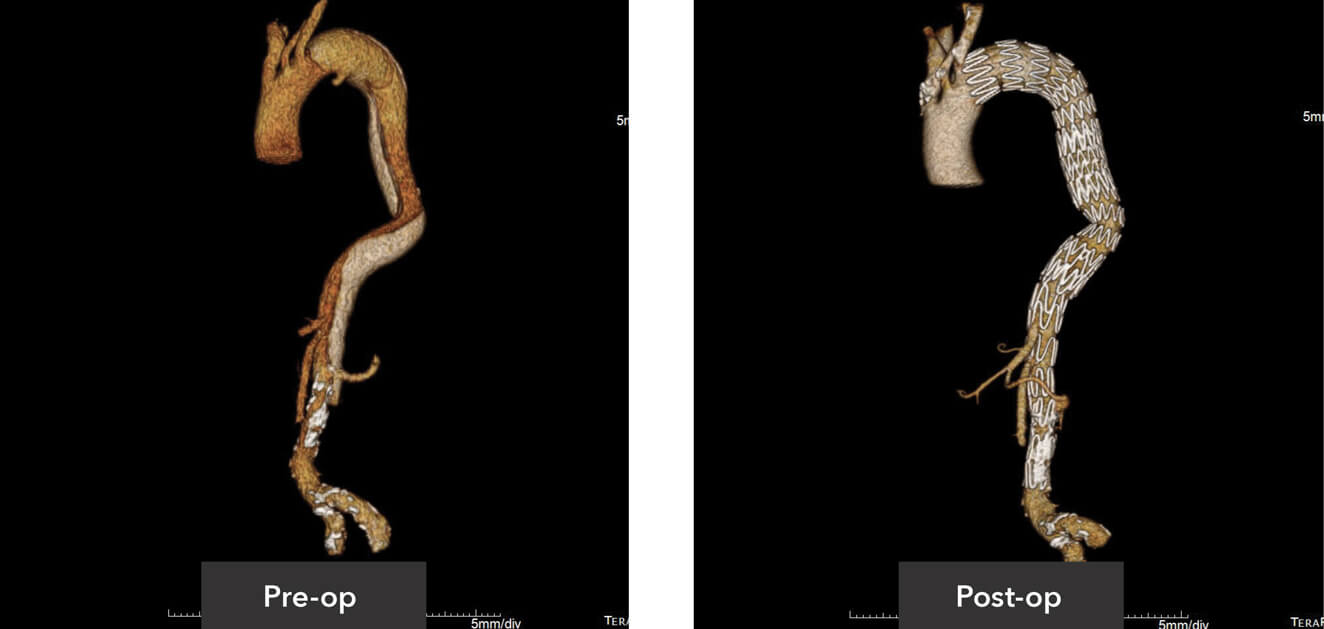

Pre-op/post-op Tera Recon imaging

Sagittal view pre-op/post-op CT imaging